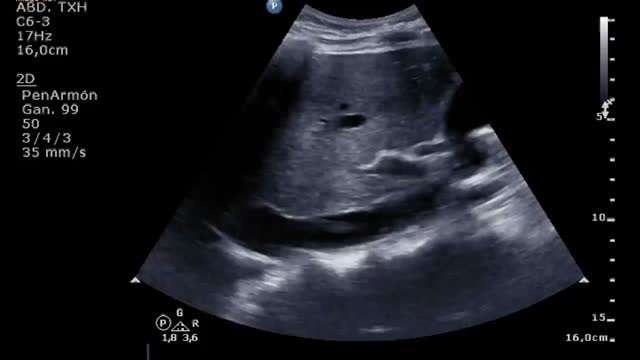

La ecografía vascular permite medir el diámetro vascular para elegir el tamaño óptimo de las cánulas (fig. 1). Para ello, se aplica la siguiente fórmula: tamaño cánula (French)=3×diámetro del vaso (mm). Se debe elegir el mayor tamaño de cánula tanto de drenaje como de retorno para proporcionar el mayor flujo posible. La punción vascular ecoguiada aumenta la seguridad y la tasa de éxito al primer intento, disminuyendo el riesgo de complicaciones locales (canalización arterial, canalización de la unión safeno-femoral o la transfijación del ligamento inguinal)11,20.